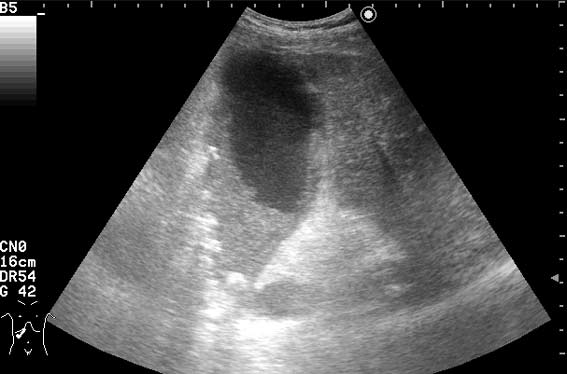

УЗИ: Острый гангренозный холецистит

Мужчина с болями вправом подреберье и температурой.

ЖКБ. Острый гангренозный холецистит?

Верно